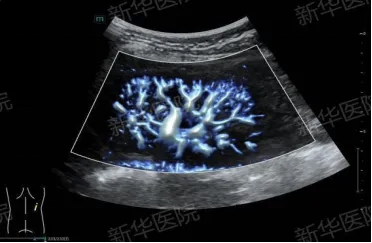

超声新武器,让我们走近看不见的肾脏

你是否担心肾脏及尿路疾病?传统检查辐射让人焦虑?在新华医院超声科有一项影像学检查的“黑科技”— 超声造影技术,可以快速精准评估尿路、肾脏发育以及肾血管异常等情况!01肾脏超声造影的原理是什么?其实肾脏超声造影原理非常简单:就是在常规超声的基础上,经过肘静脉或尿道注射小剂量的超声造影剂微泡,它们就像一个个“小气球“,随着血液流动,增强人体的血流信号,可以实时动态、灵活简便地观察肾动脉、肾脏微循环血流灌注及膀胱输尿管返流情况,提供比常规超声更丰富、更精准的影像学信息。02肾脏超声造影(1)尿路梗阻与功能评估肾积水:动态观察造影剂排泄过程,判断梗阻部位(如肾盂输尿管连接部梗阻、输尿管膀胱连接部梗阻)及分肾功能。膀胱输尿管反流(VUR):无辐射且敏感性高,尤其适合儿童尿路感染或尿道梗阻,需要多次反复随访病例。病例1:患儿,男,5岁,5年前因泌尿道感染在外院治疗后来我院随访。膀胱输尿管逆行超声造影显示:经膀胱导尿管缓慢注入少量超声造影剂后,膀胱内可见造影剂快速充盈,左侧输尿管可见全程增强,宽约3mm-3.7mm。双肾及右侧输尿管区域未见明显增强。诊断为:左侧膀胱输尿管反流(II级)(2)慢性肾病评估肾皮质微循环血供通过静脉注射超声造影剂,实时定量可视化地显示肾皮质微循环血流灌注增强-消退的过程,为慢性肾病早期诊断及监测随访提供影像学依据。病例2:患者,男,13岁,主因诊断过敏性紫癜性肾炎”2月余。超声造影显示:经静脉注射超声造影后,肾皮质8s开始增强,呈整体均匀高增强,19s达峰值,未见明显灌注缺损,静脉期及延迟期可见肾皮质增强缓慢消退。诊断:肾血流灌注正常。(3)肾血管异常肾动脉狭窄:经静脉超声造影可清晰显示肾动脉走行及血管腔充盈情况。移植肾监测:经静脉超声造影可早期发现血管并发症(如吻合口狭窄)或排异反应。病例3:患者,男,14岁,因不明原因高血压来我院就诊。超声造影显示:经静脉注入少量超声造影剂后,动脉期早期17秒左右,左肾动脉可见造影剂微泡快速连续通过。左肾动脉起始端变窄,内径约1.6mm,其远端内径约4.7mm,局部狭窄率约为66%。诊断:左肾动脉起始端狭窄。(4)肾占位性病变超声造影可以清晰显示占位内部的微循环血流灌注,通过造影剂增强-消退模式可以精准评估病灶良恶性。03肾脏超声造影独特优势实时动态成像:观察肾皮质微循环血流灌注,是否存在膀胱输尿管返流。安全性高:安全、无放射性,适合反复多次随访及肾功能不全的患者。操作便捷:实时快捷、适合床旁检查检查后即刻可获取结构化的超声诊断报告。儿童友好的影像学检查:无需镇静,全程家长可陪同,随时交流安抚患儿情绪。超声造影是评估肾脏及尿路疾病的一种绿色、安全、有效的影像学检查方法,尤其适用于慢性肾病、泌尿系梗阻性疾病及肾血管异常的诊断及随访,为患者提供更优的诊疗方案。科室介绍上海新华医院超声科依托新华医院儿科临床学科特色,在国内率先开设儿童肿瘤专科门诊及超声造影专科门诊,应用高分辨超声造影、超微血流超声成像、超声剪切波弹性成像、超声脂肪肝声衰减定量、三维超声、超声与CT/MRI/PET-CT等多模态影像融合导航等技术,大大提高了疑难病例的诊治水平,让患者得到及时精准的诊断。并参与撰写2023版欧超联EFSUMB超声造影定量分析共识、2020版世超联WFUMB肝脏超声造影指南、2021版欧超联EFSUMB儿科超声造影指南。上海新华医院儿肾脏风湿免疫科不但为慢性肾脏病患儿提供合理的治疗方案及并发症的管理,且为终末期肾病患儿选择合适的透析方案,同时还可以联合成人血液净化部为患儿提供全生命周期管理,保证患儿安全高效的透析,延长透析时长,提高患儿的期望寿命和生存质量。专科特色:幼年关节炎、过敏性紫癜、系统性红斑狼疮及疑难罕见重症免疫相关疾病的诊治,复杂泌尿道感染治疗,先天遗传性肾脏病、血尿蛋白尿表现的慢性肾脏病全生命周期管理。上海新华医院肾脏风湿免疫科下设病房、血液净化中心、腹膜透析中心、肾脏病理诊断中心、肾脏病专科门诊和肾脏专病随访门诊、肾脏病实验室。现有床位50张,血液透析机95台,CRRT机3台,多功能血液净化机2台,年血液净化65000余人次,年专科门诊量100000余人次。本专科常规开展超声引导下经皮肤肾穿刺活检术,自体动静脉内瘘、腹膜透析置管和深静脉临时/长期置管术。更多资讯可关注上海新华医院超声科官方微信